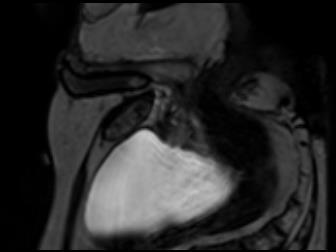

Direct automatic segmentation of objects from 3D medical imaging, such as magnetic resonance (MR) imaging, is challenging as it often involves accurately identifying a number of individual objects with complex geometries within a large volume under investigation. To address these challenges, most deep learning approaches typically enhance their learning capability by substantially increasing the complexity or the number of trainable parameters within their models. Consequently, these models generally require long inference time on standard workstations operating clinical MR systems and are restricted to high-performance computing hardware due to their large memory requirement. Further, to fit 3D dataset through these large models using limited computer memory, trade-off techniques such as patch-wise training are often used which sacrifice the fine-scale geometric information from input images which could be clinically significant for diagnostic purposes. To address these challenges, we present a compact convolutional neural network with a shallow memory footprint to efficiently reduce the number of model parameters required for state-of-art performance. This is critical for practical employment as most clinical environments only have low-end hardware with limited computing power and memory. The proposed network can maintain data integrity by directly processing large full-size 3D input volumes with no patches required and significantly reduces the computational time required for both training and inference. We also propose a novel loss function with extra shape constraint to improve the accuracy for imbalanced classes in 3D MR images.

翻译:3D医学成像的物体,如磁共振成像(MR)成像的直接自动分离,具有挑战性,因为往往需要精确地确定大量调查中大量存在复杂地理不对称的单个物体。为了应对这些挑战,大多数深层学习方法通常会大大提高其模型内可训练参数的复杂性或数量,从而提高其学习能力。因此,这些模型一般需要在运行临床MR系统的标准工作站上花很长的推断时间,并限于高性能的计算机硬件,因为它们的记忆要求很大。此外,要在这些大型模型中安装3D数据集,还要利用有限的计算机记忆,经常使用交换技术,例如补对称培训等,以牺牲从对诊断目的具有临床重要性的投入图像中获得的精细比例的几何地理信息。为了应对这些挑战,我们提出一个具有浅度记忆足迹的银色网络,以有效减少为状态性能所需的模型参数数量。这对于实际就业至关重要,因为大多数临床环境只有低端硬件,计算机功能和记忆有限。拟议的网络可以通过直接处理全尺寸三维化技术来保持数据的完整性,直接处理全尺寸的全尺寸三维的图像,从而大幅改进所需的超度变压的磁度计算。